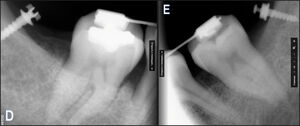

Despite that distalization is usually considered to be a non-extraction treatment option, the mechanics of tooth movement in extraction and distalization cases does incorporate sagitally directed tooth movement in the posterior segments of the arch (Figures 3A to 3E). Sagittal tooth movements generally cause positional changes of the main supporting cusps, which can lead to changes in the Vertical Dimension of Occlusion (VDO), and often cause new prematurities to be perceived within 2-3 days after appliance activation. Sometimes during distalization in severe cases, the mesiopalatal cusp of the upper first molar can cause acute pain and periodontal abscess formation in its opposing lower molar.

I. MIP/CO is recorded - to determine the presence of any contacts with excessive force, and for any rapidly rising Force Outlier contacts (Figures 3F to 3H).